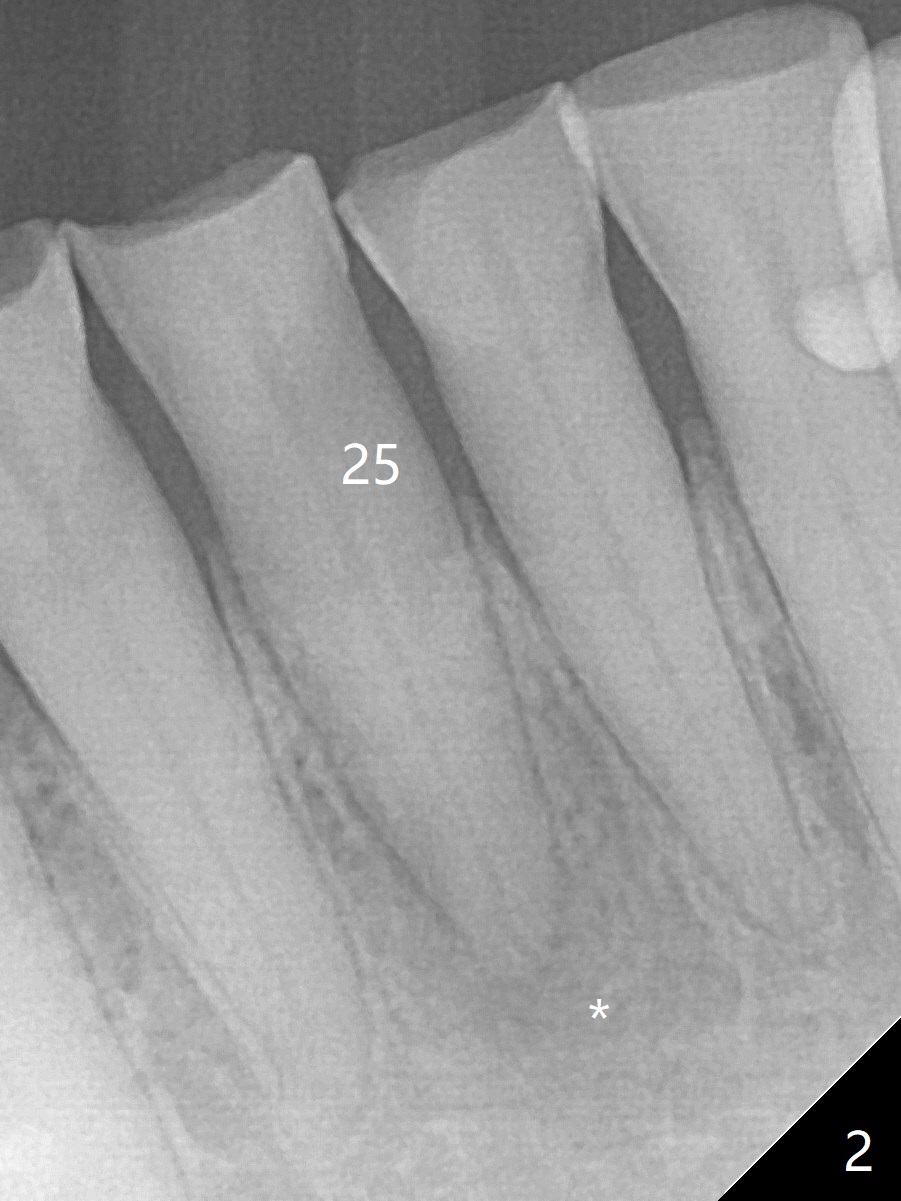

A 64-year-old man has multiple restoration and loves to eat crab. The lower incisors have severe wear. The tooth #25 is discolored with pulpal exposure and periapical radiolucency (Fig.1, 2 *). After insertion of 30/.04 master cone (Fig.3 (1 year 3 months post diagnosis)), RCT is finished with BioRoot RCS (bioceramic) and single GP (Fig.4). Nearly 10 months later, the patient returns with sinus track associated with the tooth #24 with PARL (Fig.5 *).